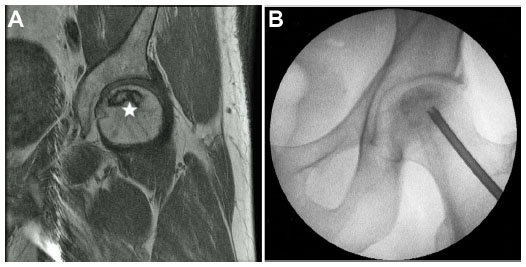

Imaging tests, to a degree, MRI and X-rays are administered to assess in presence of AVN or osteoarthritis.

Stem cells are injected directly into the damaged hip joint, guaranteeing precise delivery to the damaged tissues.